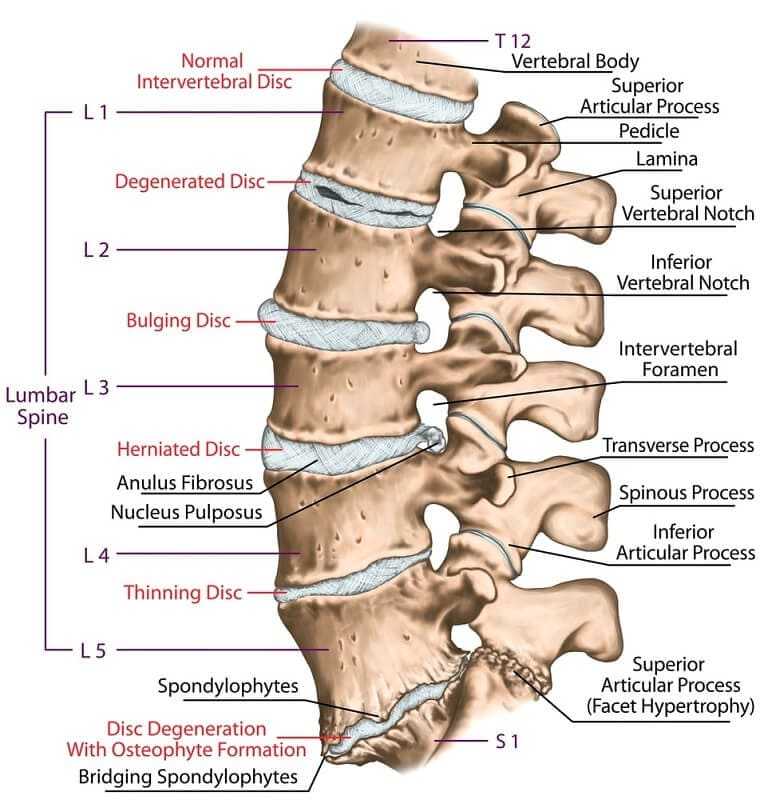

What is the difference between a bulging disc and a herniated disc?

Degenerative Disc Disease | Miami Back Pain

Lumbar Degenerative Disc Disease | Lower Back Pain | CO